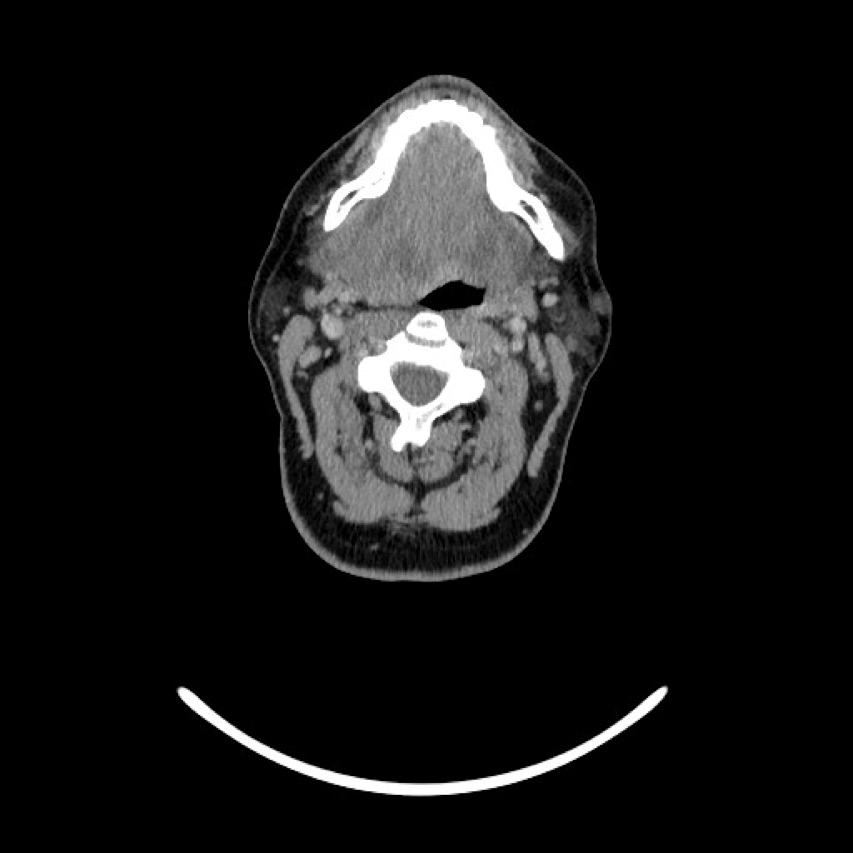

Initial investigations included blood tests and an orthopantomogram (OPG). The INR was 26. The OPG showed a large periapical radiolucency associated with the lower left lateral incisor which had previous endodontic treatment but no dental / bony cause for his advanced neck swelling was identified. A CT scan (Figure 1, 2 and 3) indicated that there were soft tissue density masses present within the floor of the mouth. They most likely represented a haematoma but an abscess could not be excluded. The airway was markedly compromised. He was immediately planned for surgical intervention with the input of the haematologist and anaesthetist, along with urgent treatment to reverse the effects of Warfarin.

Figure 3 (transverse view): CT showing a large indistinct mass / swelling of the submandibular and submental spaces with compression and deviation of the airway. Not a typical appearance of an abscess.